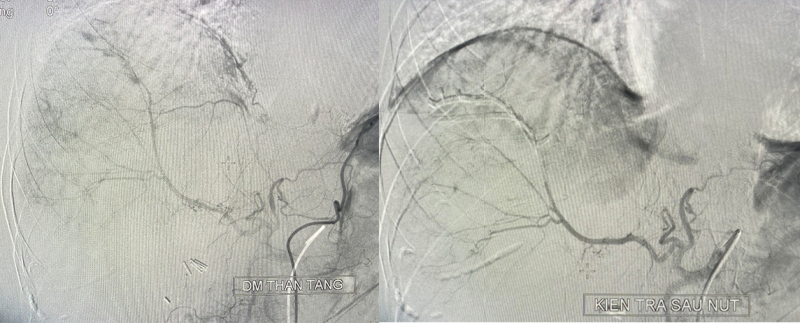

Trước nguy cơ bệnh nhân có thể tử vong do shock mất máu, kíp trực cấp cứu đã hội chẩn liên khoa: Ngoại – Điện Quang Can Thiệp – Hồi Sức Tích Cực thống nhất nút mạch cầm máu điều trị vỡ gan. Ca can thiệp nút mạch được thực hiện trong 45 phút.

Dưới sự hỗ trợ của hệ thống chụp mạch số hóa xóa nền DSA, bác sĩ điện quang can thiệp đã xác định chính xác vị trí động mạch gan bị tổn thương gây chảy máu và bơm chất tắc mạch để cầm máu. Kết quả kiểm tra ngay sau nút mạch đã không còn tình trạng chảy máu vùng gan tổn thương. Sau can thiệp 24h, người bệnh tỉnh táo, chỉ số sinh tồn ổn định, không xuất hiện chảy máu sau can thiệp.